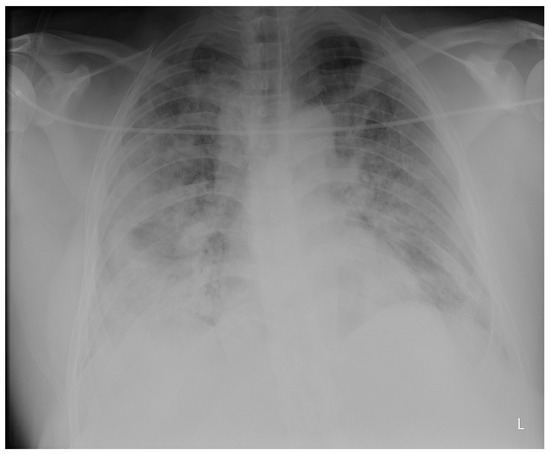

Laboratory findings were mostly normal; C-reactive protein was elevated in all patients with a mean value of 129.7 ± 80.74 mg/L. The arterial blood gas analysis showed hypoxemic respiratory failure. Chest X-rays in all patients showed bilateral inhomogeneous infiltrates (Figure 1 and Figure 2). In three patients, CTPA was performed, which ruled out pulmonary thromboembolism, but ground-glass opacifications with consolidation of the lung parenchyma were described in all of them (Figure 3 and Figure 4) [15].

Figure 2. Chest X-ray upon admittance: patient 7. Bilateral inhomogenous infiltrates typical for COVID-19 pneumonia (the “L” orientation marker indicates the left side).